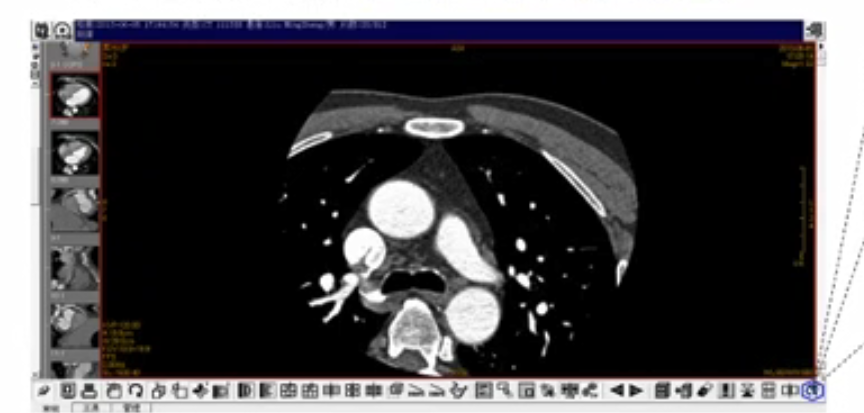

大家去医院拍片的时候,大部分情况下拍的都是X光。CT是什么呢?就是一个方舱机器,把人躺在里面把它送进去,瞬间给你照成百上千张照片。还有一种更高精度叫做MR检查要增强扫描。新冠肺炎医学诊断指南里面已经将CT检查作为一个强推荐手段,它是区别X光,普通X光存在漏诊,所以推荐度弱。但是CT检查是强推荐手段,这是第一个原因,就是为什么要用CT检查来做新冠肺炎诊断。第二个原因就是对一些早期患者,他不发热,潜伏期内它是不发热的,你用测温仪、测箱是测不出来。在实际上情况下,当你用CT检查时,他肺部已经病变了,所以就是CT检查可以有效地去发现和甄别这些早期患者。这就是我们为什么要用CT数据进行AI新冠肺炎辅助诊断的重要原因。

人躺进方舱进行医学影像检查设备拍CT,之后把数据上到PACS系统。PACS系统就是影像管理系统。在传统方式下影像管理系统医学影像医生进行筛查诊断,全过程下来至少要12分钟,然后才能有手工报告。在上千张片子下,工作量特别大,需要不停的翻。有了AI方式之后基于我们CT影像,数据拿到华为AI服务,进行AI辅助诊断我们能实现秒级返回,在10秒到20秒之间,我们就能把这个诊断结果给返回诊断。再加上医学影院医生进行确认,我们就可以把结果给输出,全流程大概只有两分钟。华为AI做的只是辅助诊断,包括业界AI也是一样,只是做辅助诊断,并不能做替代诊断。